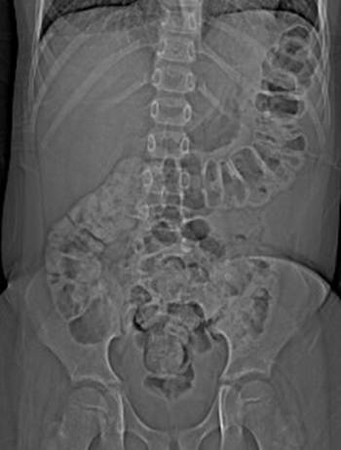

Abdominal x-ray of a young boy with acute, severe abdominal pain, demonstrating stool throughout the colon and rectum

From the collection of Dr KuoJen Tsao; used with permission